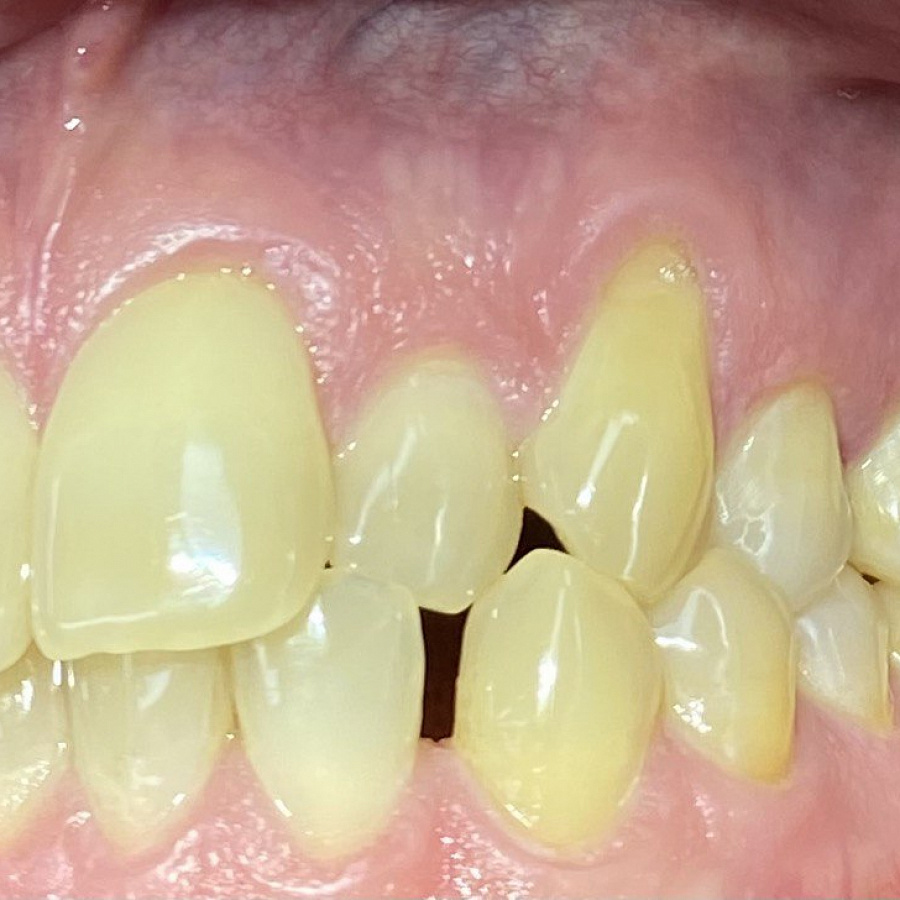

Пациент обратился с жалобами на неровные передние зубы верхней и нижней челюстей.

сужение зубных рядов,

обратное перекрытие в области фронтальных зубов слева,

разворот по оси передних зубов верхней и нижней челюстей,

стираемость эмали зубов,

индивидуальную микродентию 12 и 22 зубов.